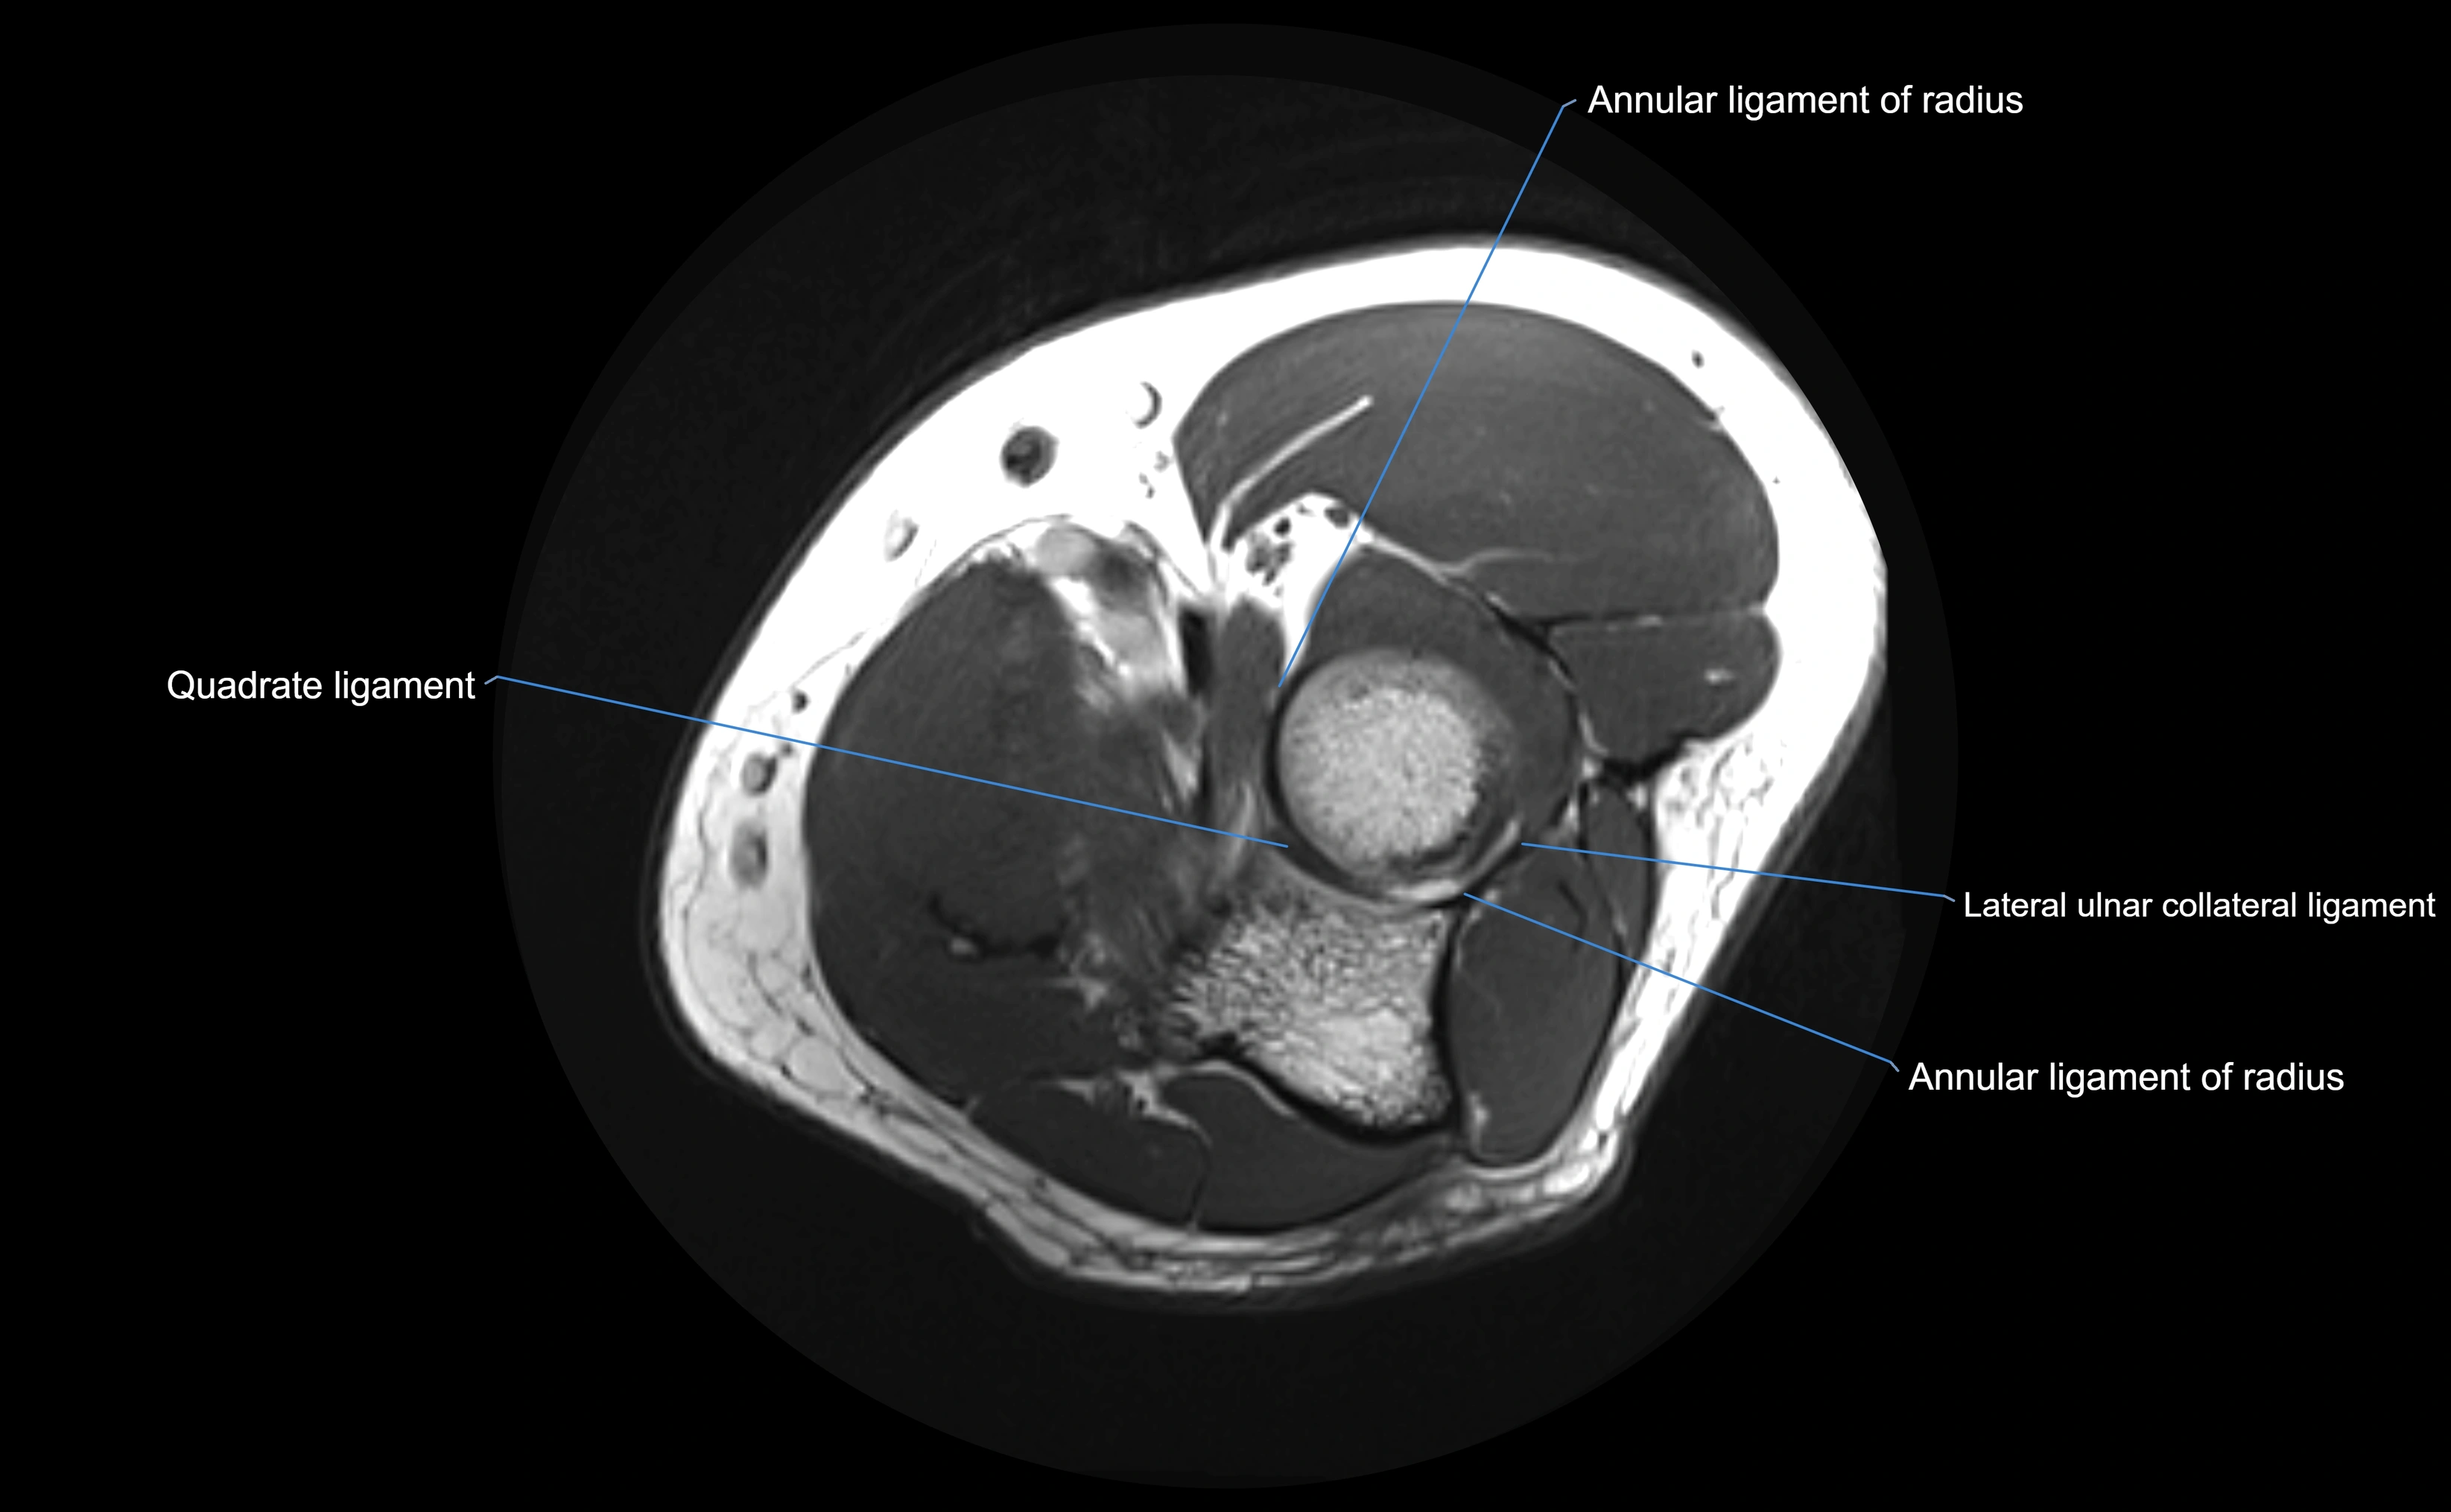

MRI images

image